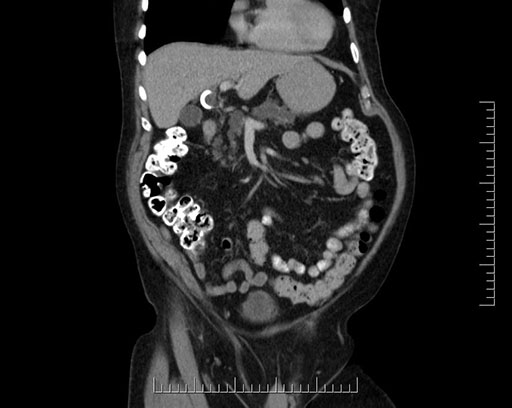

Coronal - stented